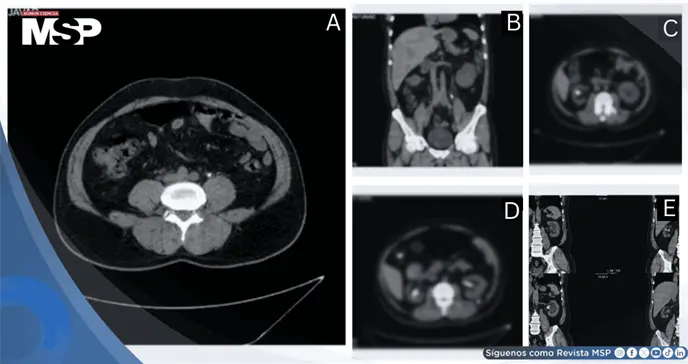

Se realizó tomografía computarizada sin contraste como modalidad de imagen primaria, seleccionada por su precisión superior en la detección de carga litiásica, hidronefrosis y complicaciones potenciales. Los hallazgos revelaron:

Riñón izquierdo: Cálculo de 15 × 8 mm en uréter medio, causando hidronefrosis severa con signos inflamatorios en el sistema colector

Riñón derecho: Cálculo de 13 × 10 mm en pelvis renal, causando hidronefrosis leve